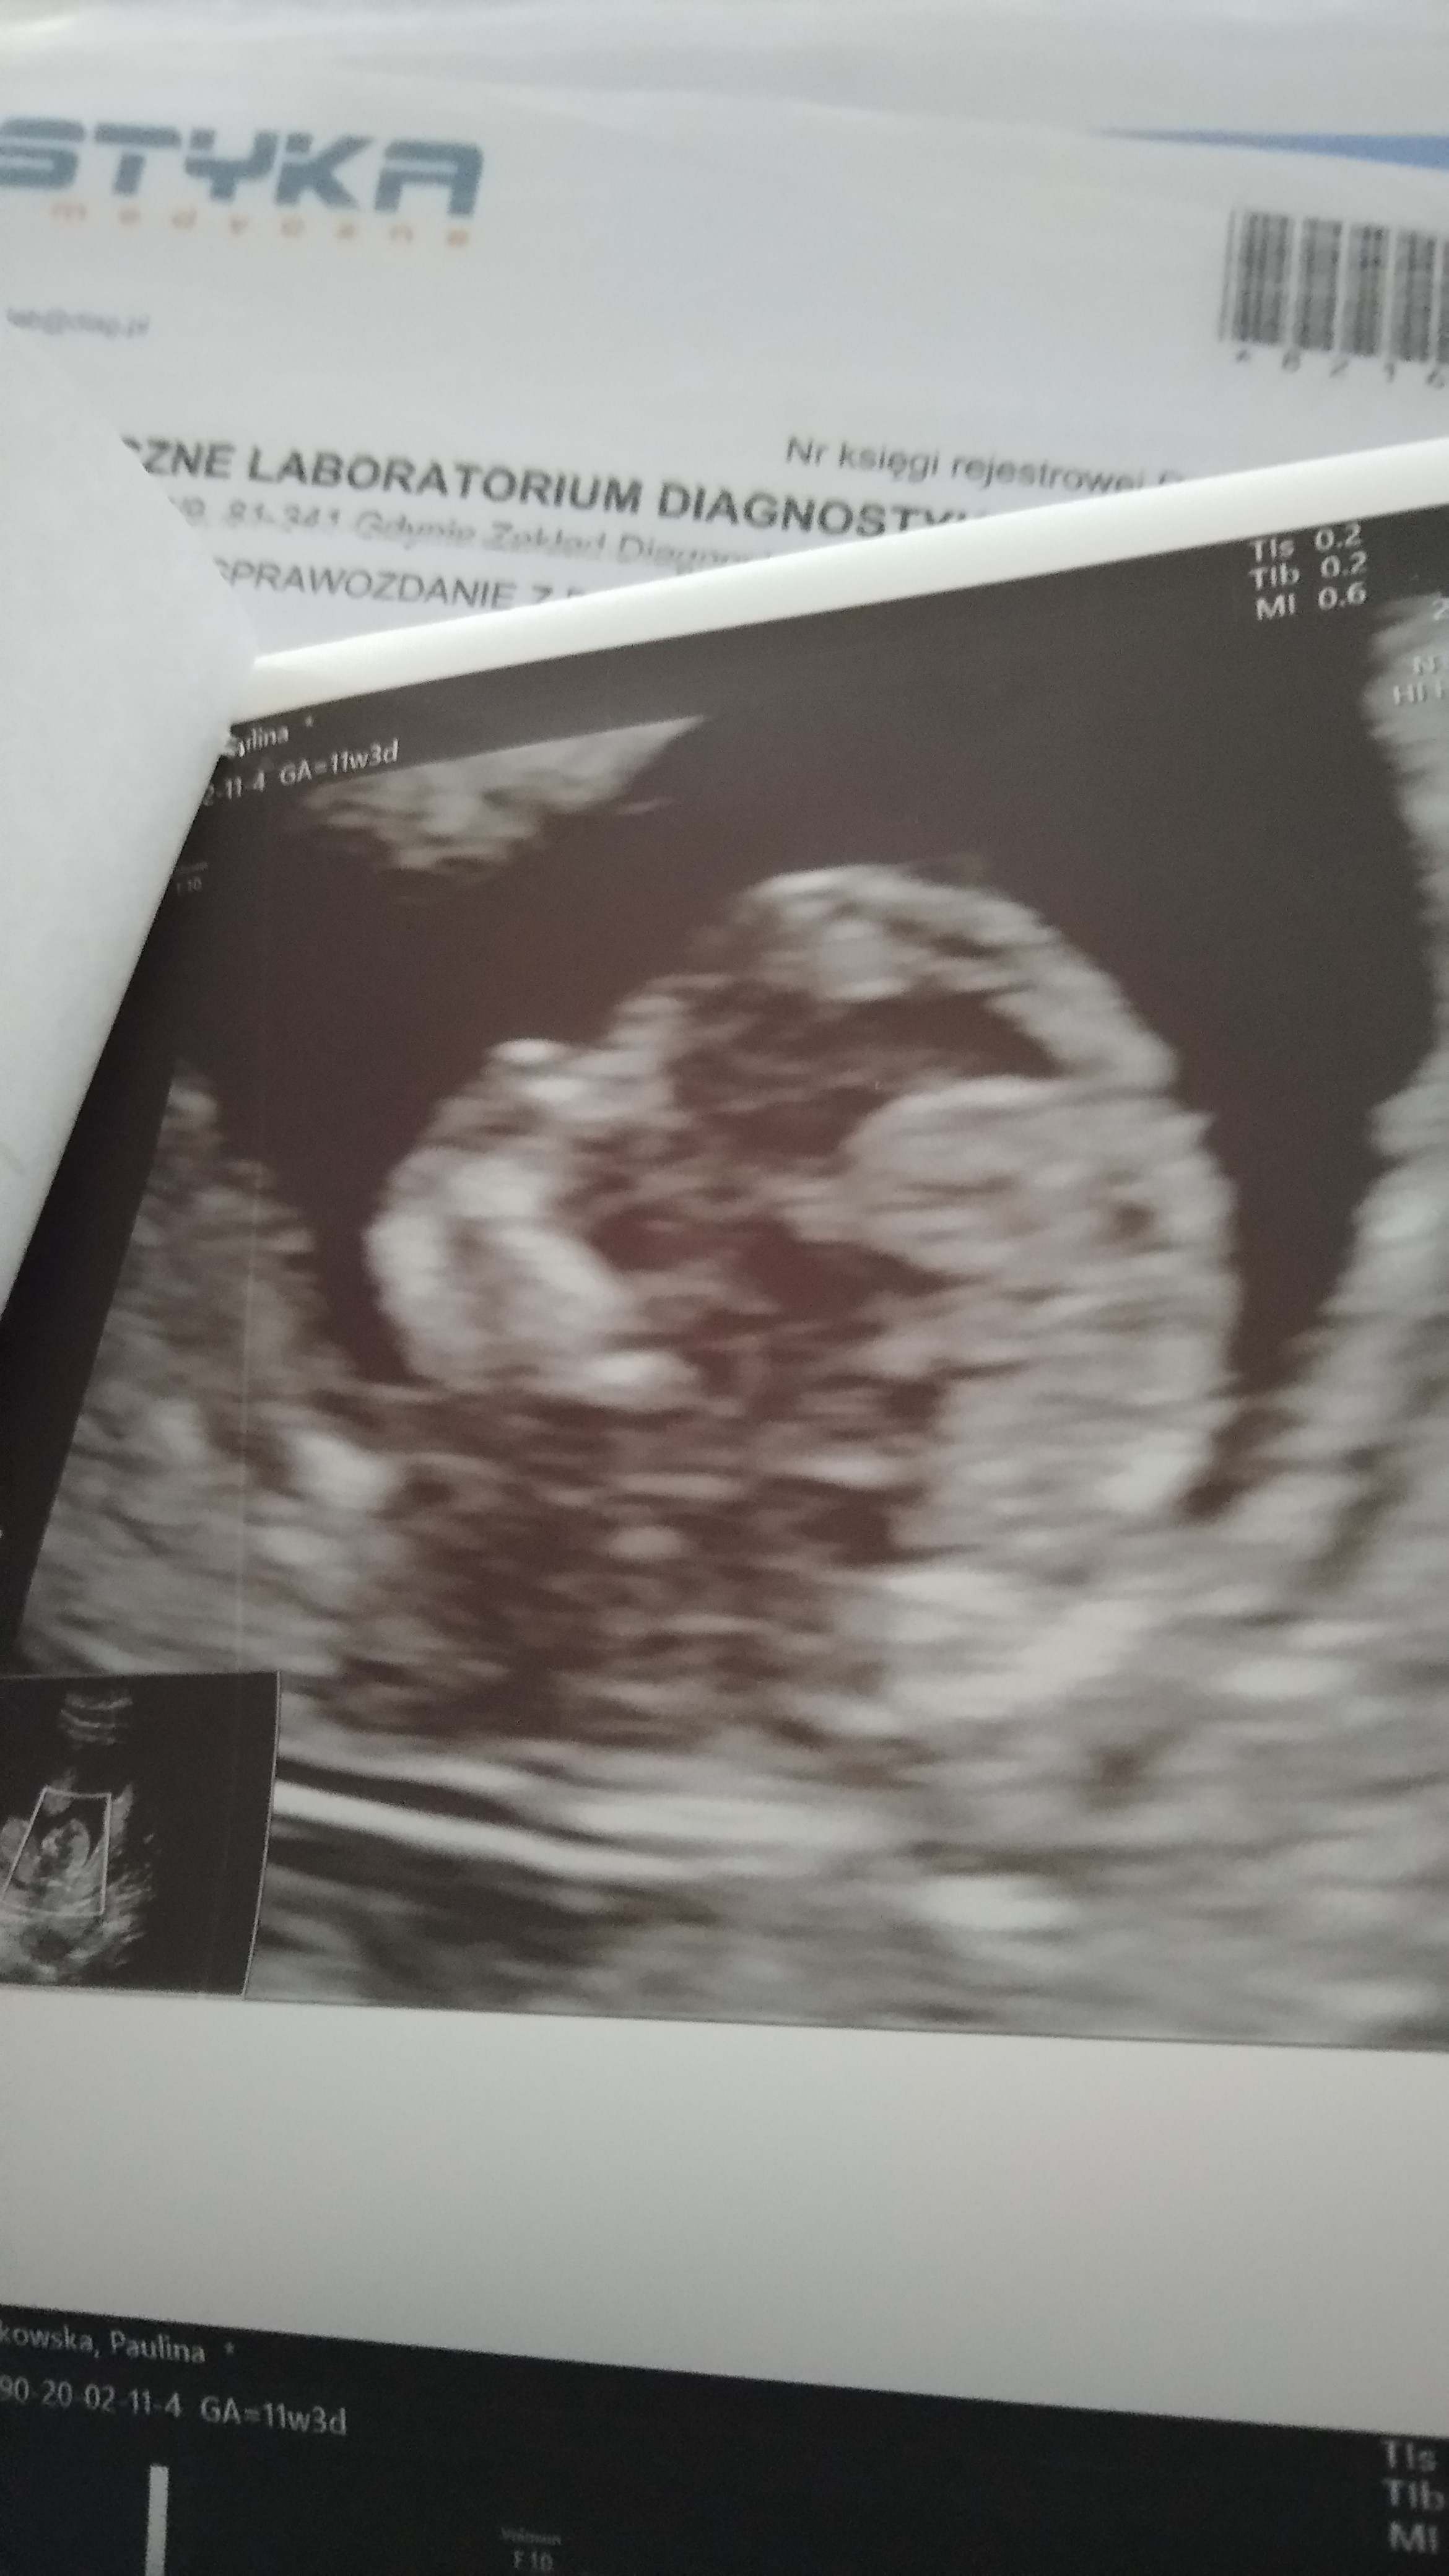

Jestem już po badaniach prenatnalnych

odetchnęłam narazie bo wszystko wygląda dobrze, przyziemność 1,2 , kość nosowa widoczna, ogólnie wszystko jak trzeba,lekarka nie ma zastrzeżeń. Maluch ma już 6cm

teraz około tydzień muszę czekać na pappa ale mam nadzieję że to tylko formalność. Uff... A oto moje maleństwo